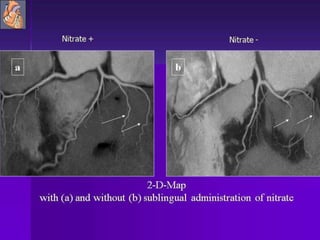

Coronary Angiography